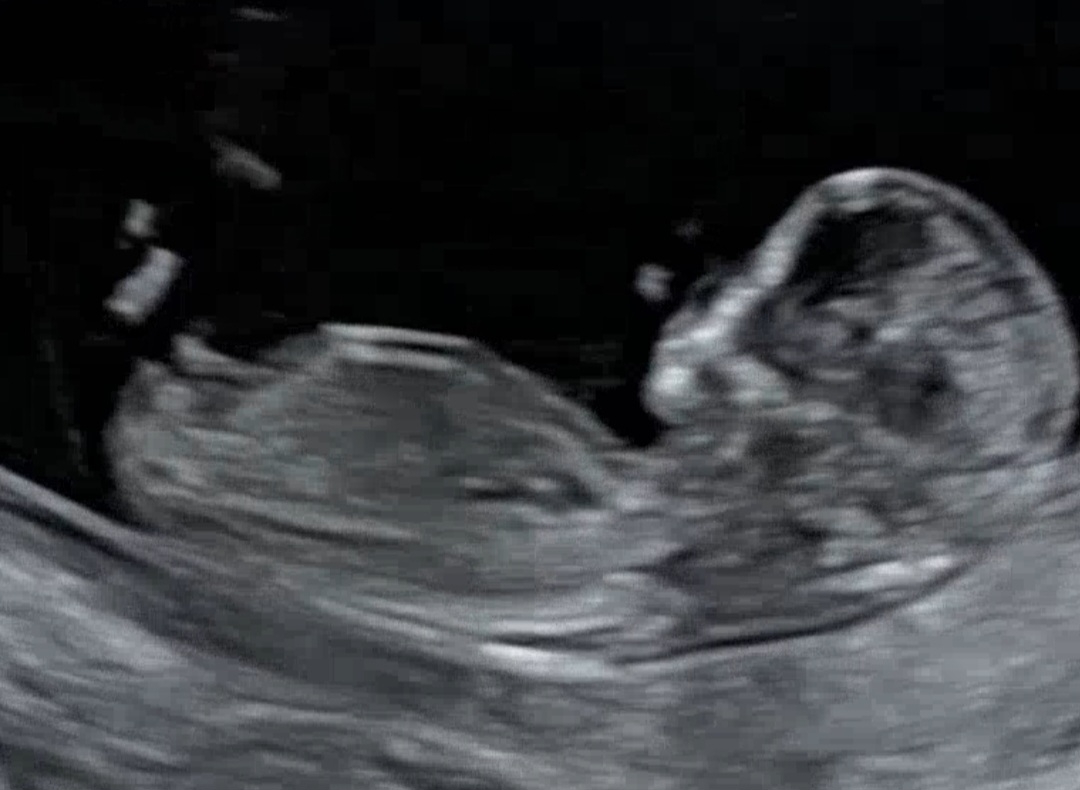

11주6일차 각도법 봐주세요~

아들일까요 딸일까요?! 위에 끝에 올라간것이 아들같기도하고.. 각도법고수님들 한번 봐주세요😊

아들이용 곰방대 처럼생기믄 아덜이더라구여 -아들둘맘-